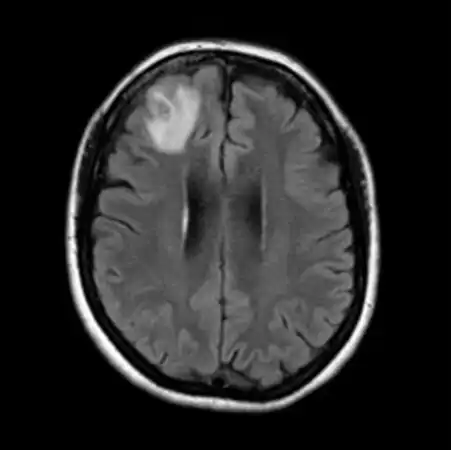

That brain scan turned up a ghostly glow in her frontal lobe. It could have been cancer, an abscess or another affliction, Senanayake says. “No one thought it was going to be a worm.”

An MRI of the woman’s brain showed a lesion (light gray area). While operating on her, doctors removed a living worm from within the lesion.M.E. HOSSAIN ET AL/EMERGING INFECTIOUS DISEASES 2023

During a biopsy of the woman’s brain, her neurosurgeon spotted a suspicious stringlike structure and plucked it out with forceps. It was pinkish-red, about half the length of a pencil — and still alive.